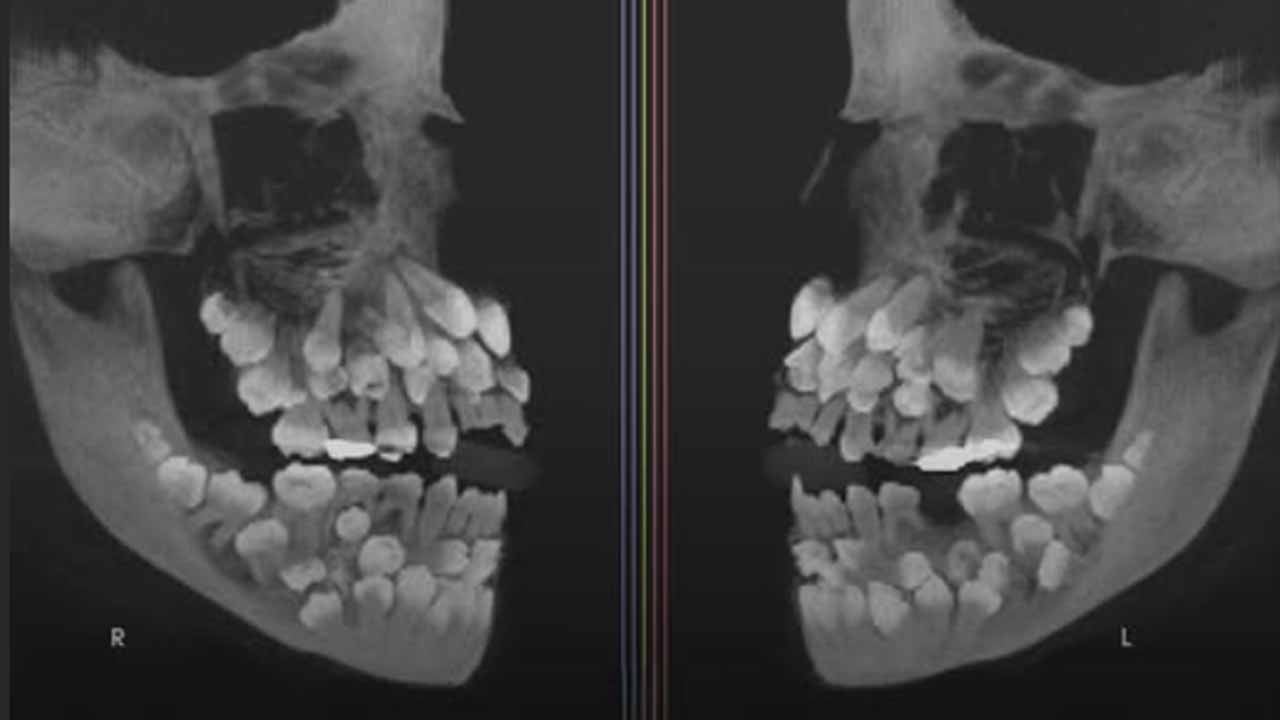

Yayınlanan ortodontik vaka raporuna göre, 11 yaşındaki bir kız çocuğu, on sekiz bebek dişi, otuz iki kalıcı diş ve otuz bir sayısal dişle şimdiye kadar kaydedilen en nadir diş anomalilerinden birine sahip olarak tespit edildi.

Genetik testler, kromozom dokuz üzerinde perisentrik bir terslik olduğunu ortaya koyarken, herhangi bir sendromla ilişkili olmadığı belirlendi.

Bu durum, sendromsuz çoklu hiperdontianın gerçek bir örneği olarak kayıtlara geçti.

Tedavi süreci, fazla dişlerin cerrahi olarak çıkarılmasını ve işlevsel ısırığın yeniden oluşturulmasını gerektirdi; sürece cerrahlar ve diş uzmanları koordineli şekilde dahil oldu.